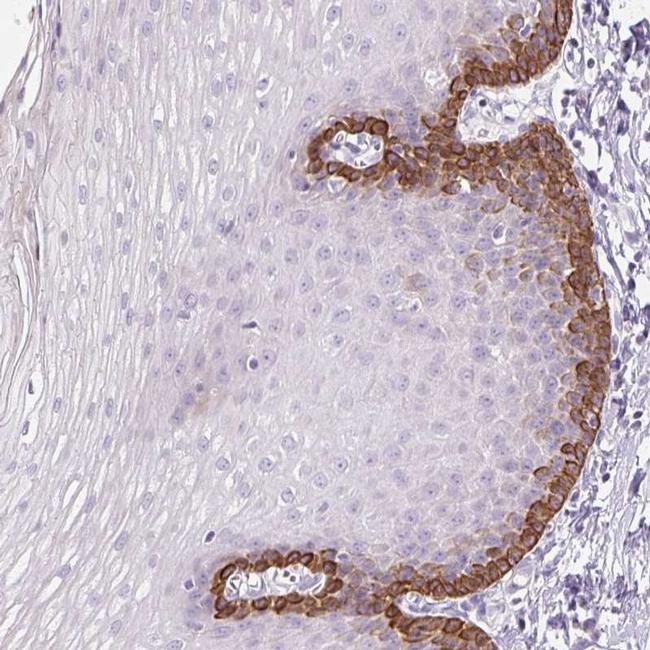

- Immunohistochemical staining of NFE2L3 in human esophogial tissue shows strong cytoplasmic positivity in basal squamous epithelial cells. Samples were probed using a NFE2L3 Polyclonal Antibody (Product # PA5-63201).